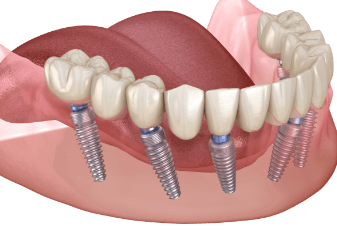

השתלת שיניים All on 4 או All on 6

השתלת שיניים All on 4 או All on 6 - המדריך עם כל המידע הרפואי והמעודכן בעבר הרחוק מי שאיבדו שיניים היו צריכים פשוט להסתדר בלעדיהן, בהמשך הופיעו שיניים מלאכותיות שעוגנו אל שיניים טבעיות שעדיין נמצאו בפה וגם מערכות של שיניים תותבות שנ